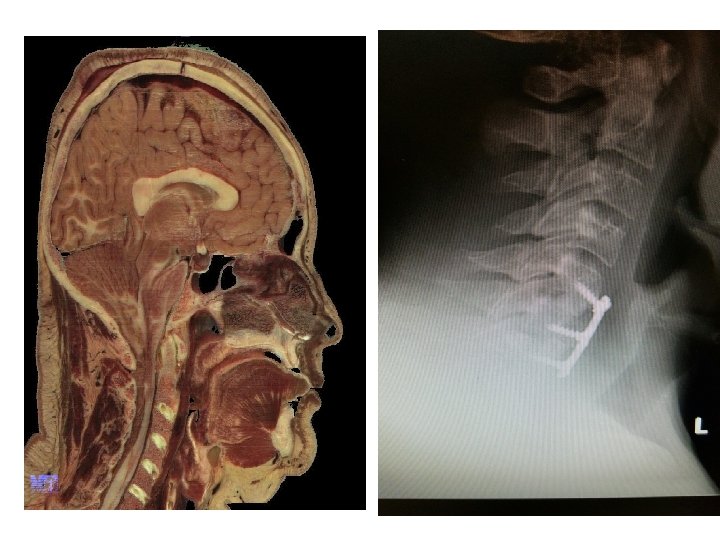

Blocked Airway

Trachea Blockage Tracheostomy Creates a second airway